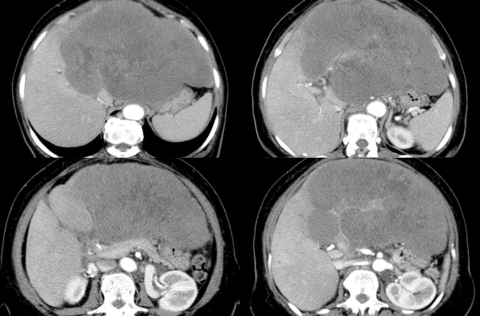

Fig. 3. Volumineux lymphome B diffus à grandes cellules du foie.